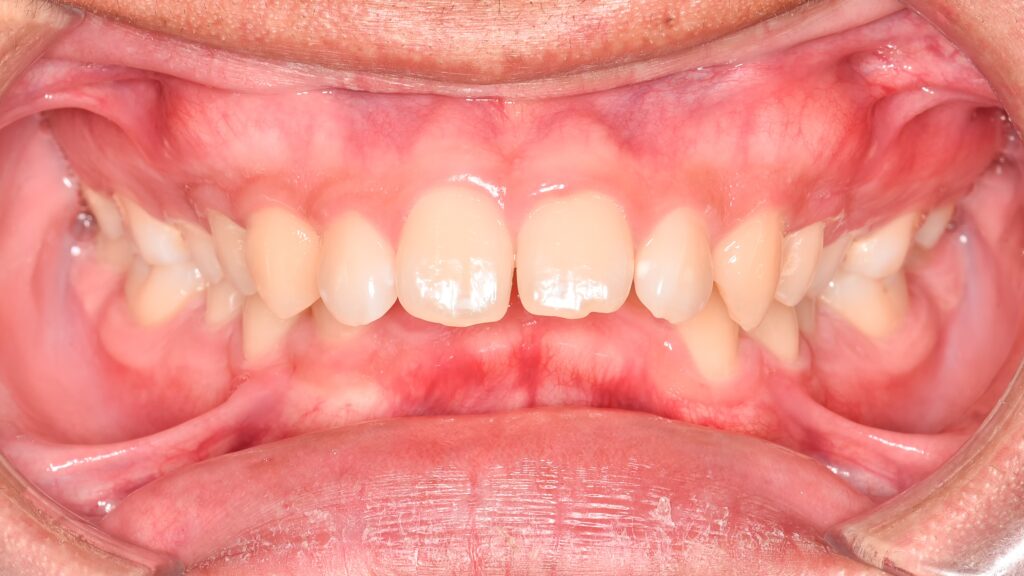

La reconstrucción dental es uno de los tratamientos más versátiles y resolutivos en odontología moderna. Cuando un diente se ha fracturado, debilitado o presenta una caries extensa, disponer de un procedimiento que permita devolverle su forma, su función y su […]